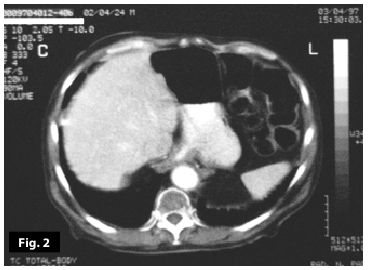

Figure1

Figure2

Figure1-2